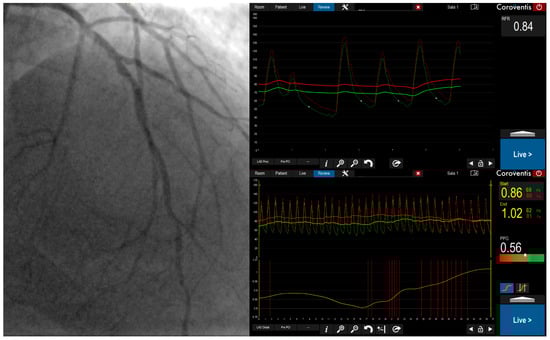

The Pullback Pressure Gradient: Transforming Invasive Coronary Physiology from Lesion Assessment to Disease Pattern Characterization—A Perspective

This perspective comprehensively analyzes the invasive pullback pressure gradient (PPG), a novel physiological index that characterizes the longitudinal distribution of coronary artery disease and guides revascularization strategy modified in 14% of patients in the PPG Global Registry based on PPG assessment. We trace

This perspective comprehensively analyzes the invasive pullback pressure gradient (PPG), a novel physiological index that characterizes the longitudinal distribution of coronary artery disease and guides revascularization strategy modified in 14% of patients in the PPG Global Registry based on PPG assessment. We trace the historical development from subjective pullback curve analysis to a standardized, quantitative metric and describe the procedural aspects of both motorized and manual PPG acquisition. We synthesize evidence supporting PPG’s clinical utility in predicting post-percutaneous coronary intervention outcomes, guiding revascularization decisions, and improving patient-centered outcomes. A central focus is PPG’s mechanistic role in explaining the physiological basis of discordance between fractional flow reserve (FFR) and instantaneous wave-free ratio (iFR), linking focal disease to FFR-positive/iFR-negative patterns and diffuse disease to FFR-negative/iFR-positive patterns. We conclude that PPG represents a fundamental advancement in coronary physiology, shifting clinical focus from individual stenoses to overall disease patterns. This paradigm shift provides deeper understanding of coronary artery disease pathophysiology and offers a powerful predictive tool to guide personalized revascularization strategies. Prospective randomized trials will be essential to solidify its role as a cornerstone of modern interventional cardiology practice.